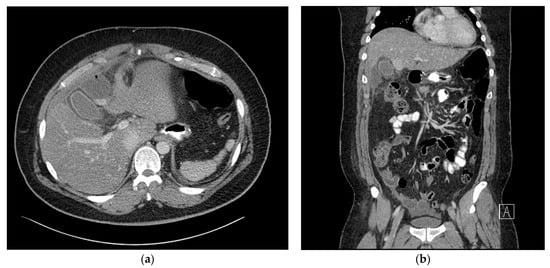

On postoperative day 3, the patient had a fever of 38 °C, WBC count increased to 14.3 × 103/μL, and the C-reactive protein level increased to 23.7 mg/dL. The following day, abdominal CT with oral water-soluble contrast media was performed, which showed a 50 × 40 mm sized abnormal fluid collection in the right subhepatic space. Extra-luminal leakage was not observed (Figure 2b) and apart from the fluid collection in the right subhepatic space (Figure 2a), there was no fluid collection adjacent to the resected stomach. Percutaneous drainage was attempted, but the procedure failed as the needle did not reach the fluid due to the patient’s thick abdominal wall. We decided to observe the patient without the use of antibiotics.

Figure 2. (a) Axial view of the abdominal computed tomography (CT) scan at the subhepatic level, showing a 50 × 40 mm sized abnormal fluid collection in the right subhepatic space. (b) Coronal view of the abdominal computed tomography (CT) scan showing no extraluminal leakage.